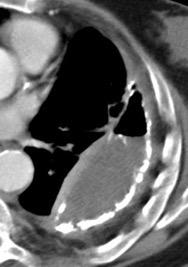

En el hemotórax, los elementos formes de la sangre tienden a depositarse en la parte más declive

Polireddy K et al. Blunt thoracic trauma: role of chest radiography and comparison with CT findings and literature review . Emerg Radiol 2022.

Neumo-Hemotórax

Sin fracturas: 6,7%

1-2 fracturas: 24,9% + de 3 fracturas:81,4%

Colección pleural

Hemorrágica.30-70 UH

Extravasación iv con sangrado activo.>90 UH “Simpático”..<15 UH

Urogénico…< 15 UH

Entérico.. +/- 15UH

Biliar, quiloso..<0 UH

5% de los traumas cerrados

Khoriati A, et al. Journal of Emergencies, Trauma, and Shock. 2013 .

Polireddy K et al. Blunt thoracic trauma: role of chest radiography and comparison with CT—findings and literature review . Emerg Radiol 2022.

Durso AM et al. Penetrating Thoracic Injury. Radiol Clin N Am 2015.